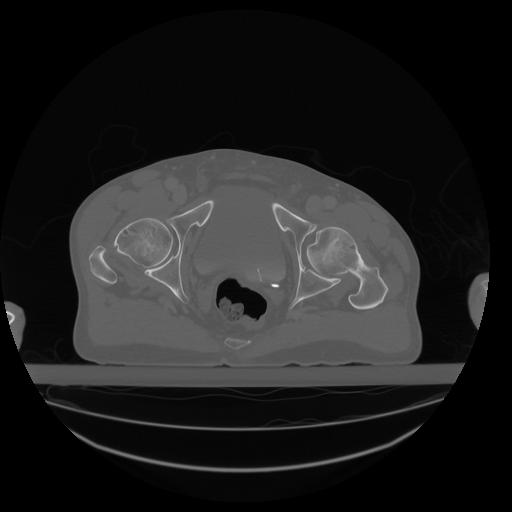

34 CUERPO,CE,Vol,1.0,CUERPO,,